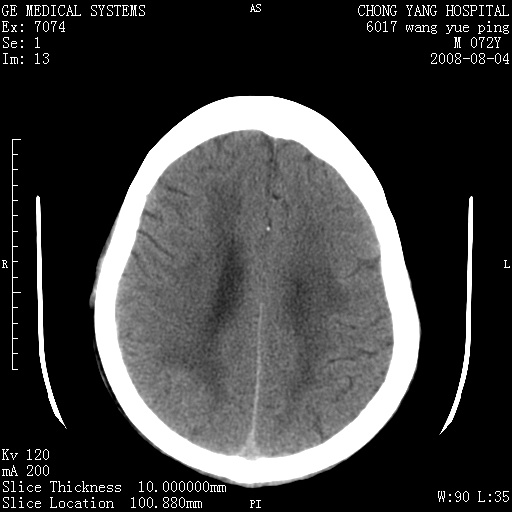

标题: CT14987:M72Y,头痛头昏,BP220/110. [打印本页]

标题: CT14987:M72Y,头痛头昏,BP220/110.

1)考虑左侧小脑脑梗塞。2)脑白质病。3)脑萎缩。4)双侧鼻腔新生物(息肉?)并阻塞性副鼻窦炎。

1.左侧小脑大面积梗塞;2.左侧基底节区腔梗;3.白质疏松;4.脑萎缩;5.慢性副鼻窦炎

1)考虑左侧小脑脑梗塞,建议治疗后复查除外其他,左基底节区腔隙性脑梗塞2)脑白质变性3)脑萎缩。4)双侧鼻腔新生物(息肉?)并阻塞性副鼻窦炎。